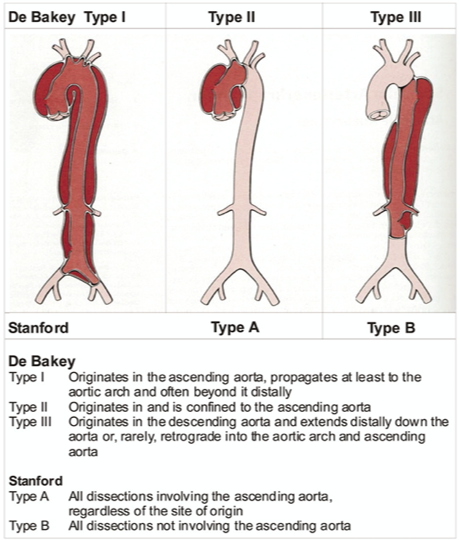

What does this refer to (in terms of aortic dissection)

Most simplified classification system EVER!

Stanford system divided into:

Stanford Type A (proximal)

_______________

Involves the Ascending aorta

What does this refer to (in terms of aortic dissection)

Most simplified classification system EVER!

Stanford system divided into:

Stanford Type B (distal)

__________

Does NOT involve the ascending aorta

What does this refer to

Stanford Typing System Aortic Dissection

Tx choice often depends on location

Stanford type A (ascending aortic) dissection

Immediate Open surgical mgmt superior to medical mgmt

Uncomplicated Stanford type B (distal aortic)

Medical mgmt preferred over surgical intervention

Repair if evidence of rupture or vessel occlusion

Medical management of aortic dissection